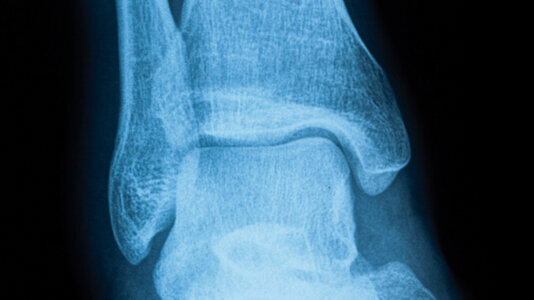

L’équipe de Gordana Vunjak-Novakovic (de l’université Columbia, New York) a réussi à ensemencer un os de veau, débarrassé de ses cellules, avec des cellules souches adultes humaines de la moelle osseuse.

Préalablement découpé aux dimensions voulues, cet os a été placé dans un bioréacteur fait, lui aussi, sur mesure. Le bioréacteur a apporté en profondeur les nutriments nécessaires à la prolifération et à la différenciation des cellules osseuses. Au bout de cinq semaines, un os vivant avait remplacé la structure inerte initiale. Guy Daculsi de l’Inserm considère que le processus est maintenant au point : « Des sociétés se positionnent déjà à l’étranger pour reproduire des structures osseuses plus complexes en bioréacteur. En Europe, le projet “Reborne”, coordonné par l’Inserm, a lancé cinq essais cliniques de reconstitution osseuse chez l’homme, pour les chirurgies orthopédique et maxillo-faciale ».

L’allogreffe fait rêver tous les implantologistes par son infinie disponibilité en termes de quantité et par l’inexistence ...